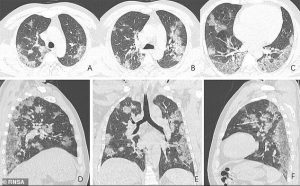

VIDEO: Cum arată plămânii unui bolnav care s-a vaccinat în comparație cu cei ai unui pacient nevaccinat. Diferența e uriașă!

Vaccinarea face diferența atunci când vine vorba de modul în care SARS-CoV2 atacă organismul. Numeroase studii au dovedit beneficiile vaccinării. Oamenii care s-au vaccinat au șanse mai mici de infectare, șanse reduse de a transmite virusul și șanse foarte mari să facă o formă foarte ușoară a bolii. Directorul medical al Spitalului de Boli Infecțioase